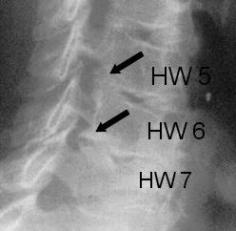

Procedure:

The operation gets performed by the use of general anaesthesia. The patient gets bedded lying on the belly whilst the head and the cervical spine get stretched. With the help of a surgical microscope the surgeon will carefully separate the thick muscles of the neck. During the entire operation the surgeon has the possibility to use an X-ray to ensure to be on the correct level. In the further procedure the surgeon cuts away the lateral parts of the vertebral arches which lowers the pressure on the nerve- root and releases the discomfort in most of the cases. This operation is also called Frykholm operation and commonly used due to the fact that the surgeon does not have to implant any artificial substances.